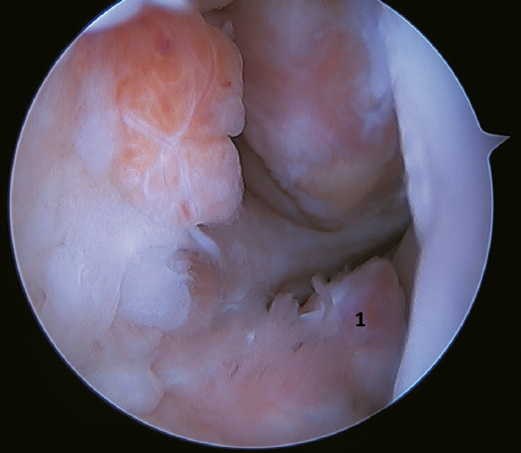

The main indication for this repair is rupture of the upper fascicle of the ATFL from its fibular insertion, with good tissue quality of the remaining ligament (Figure 3).